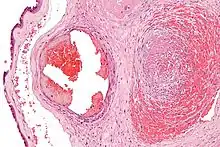

| Intermediate magnification micrograph of the placental disc showing a thrombosed fetal vein, as may be seen in fetal thrombotic vasculopathy. H&E stain. | |

It can be diagnosed by histomorphologic examination of the placenta and is characterized by fetal vessel thrombosis and clustered fibrotic chorionic villi without blood vessels.